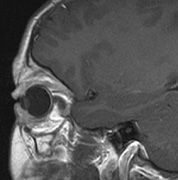

Optic nerve gliomas may involve the optic chiasm and be associated with endocrine disorders or nystagmus.68–70 Surgical excision of chiasmal gliomas (Fig. 6) carries a high risk of visual loss. Invasion of the hypothalamus or the third ventricle carries a poor prognosis, with greater than 50% 15-year mortality rate.71 One review of radiation treatment for chiasmal gliomas collated data from small case series and found no significant long-term improvement in visual function, progression, or mortality with radiation treatment.71 Other reports suggest that radiation doses over 4500cGy improve symptoms and slow progression of chiasmal gliomas over several years.72 Adequate tumor coverage by radiotherapy results in irradiation of normal brain and nearly all children need hormone replacement.73 Chemotherapy is an alternative.74,75

Fig. 6. Surveillance images of a 12-year-old girl with NF1 and an optic nerve glioma which has extended to involve the chiasm. Pre- (a) and postcontrast (b) T1-weighted coronal images reveal a large suprasellar mass with an enhancing component (arrow) seen separately from the normally enhancing pituitary gland. (c) Axial scans through the suprasellar cistern show the tumor is high signal on T2-weighted scans. (d) Enlargement of the chiasm, optic nerve and hypothalamus is visible on the post-contrast T1-weighted sagittal image. Although optic nerve glioma usually has a good prognosis (with visual function often remaining stable in the absence of any intervention66,67), chiasmal involvment is a poor prognostic indicator. A sign of chiasmal involvment may be new onset of endocrine disorders or nystagmus. Surgical excision of chiasmal gliomas carries a high risk of visual loss.68–70